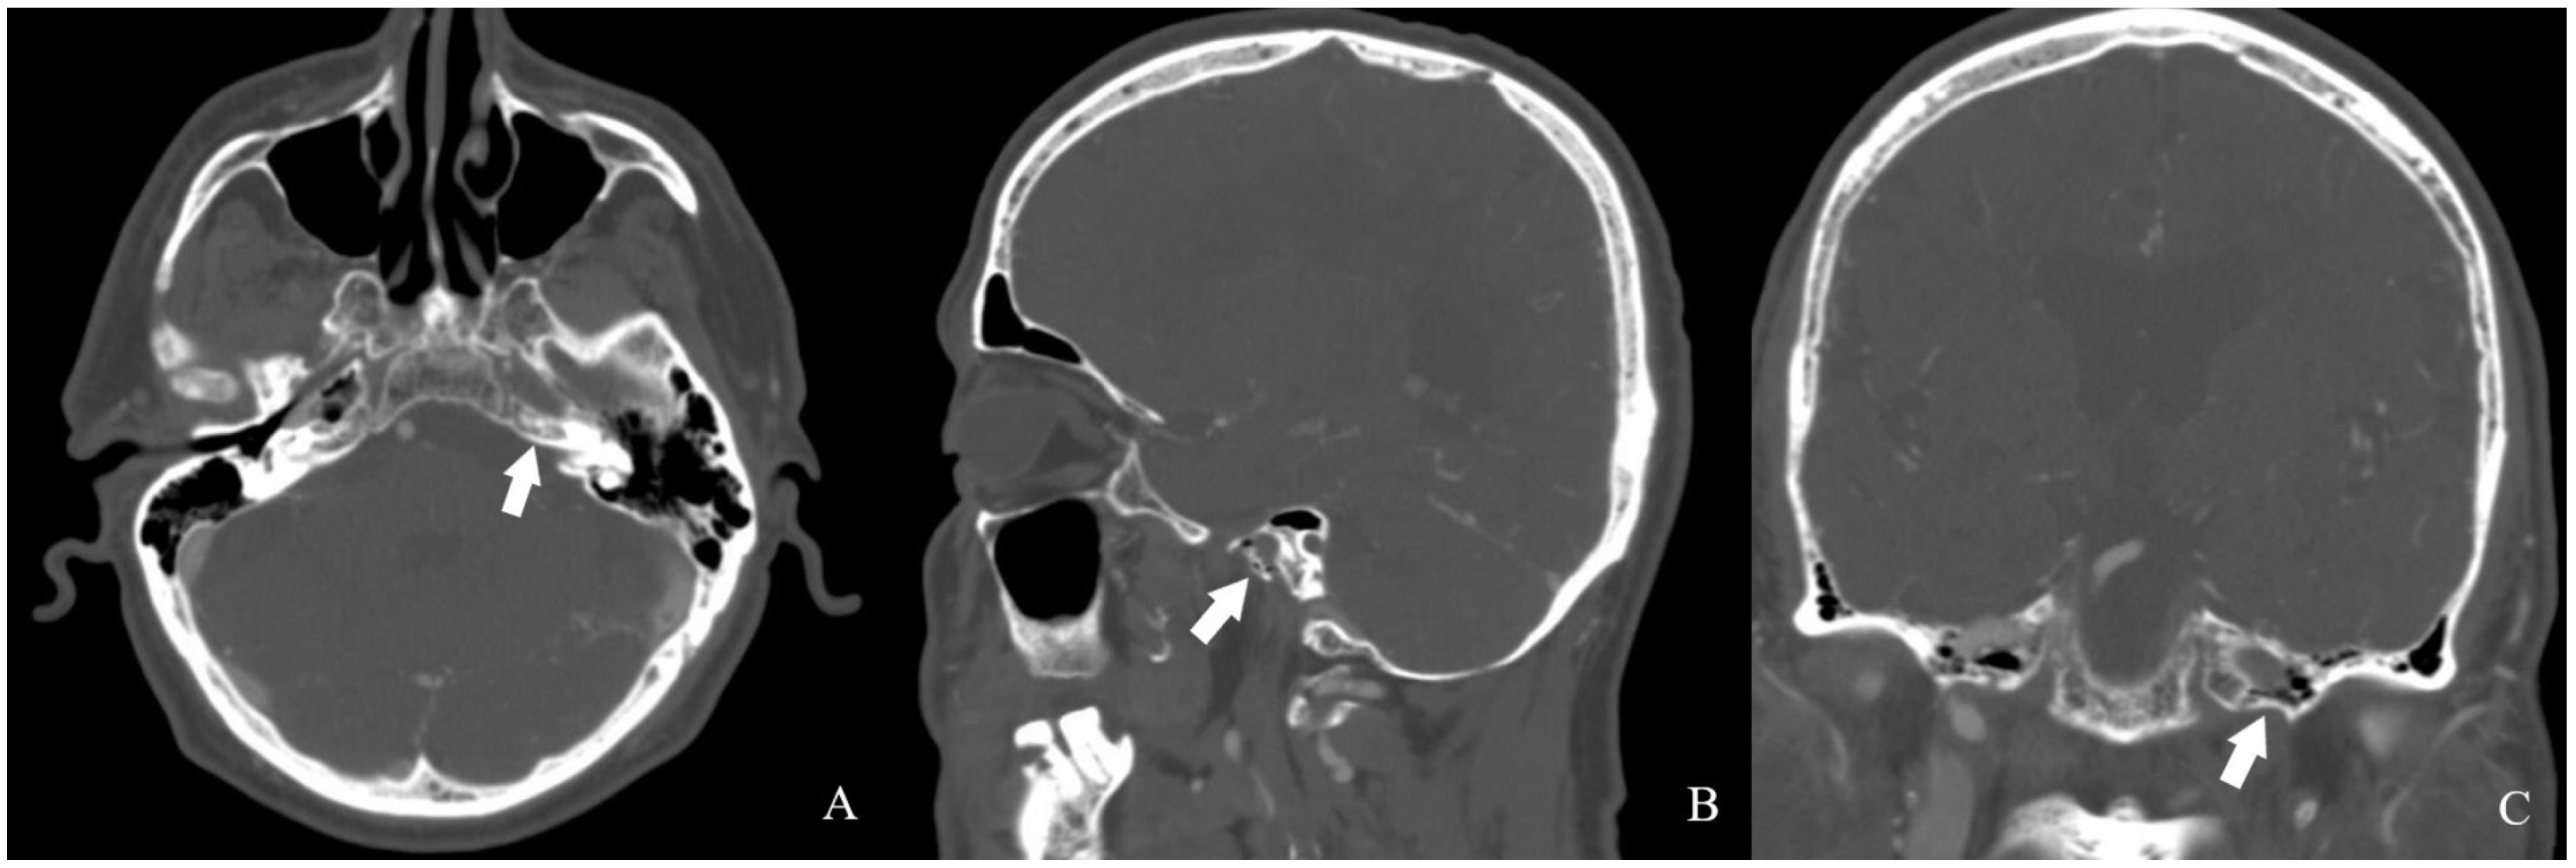

A review of the patient’s radiologic records revealed a cranial CT angiography performed nine years ago. Imaging showed no contrast in the left internal carotid artery. In addition, the left petrosal carotid canal was found to be intact (Figure 5 and Figure 6).

Figure 5.

CTA image obtained from the patient nine years ago [White arrow: indicates a filling defect beginning at the proximal segment of the ICA].

Figure 6.

The patient’s CTA images [(A) axial, (B) sagittal, (C) coronal] revealed a preserved carotid canal [white arrow].